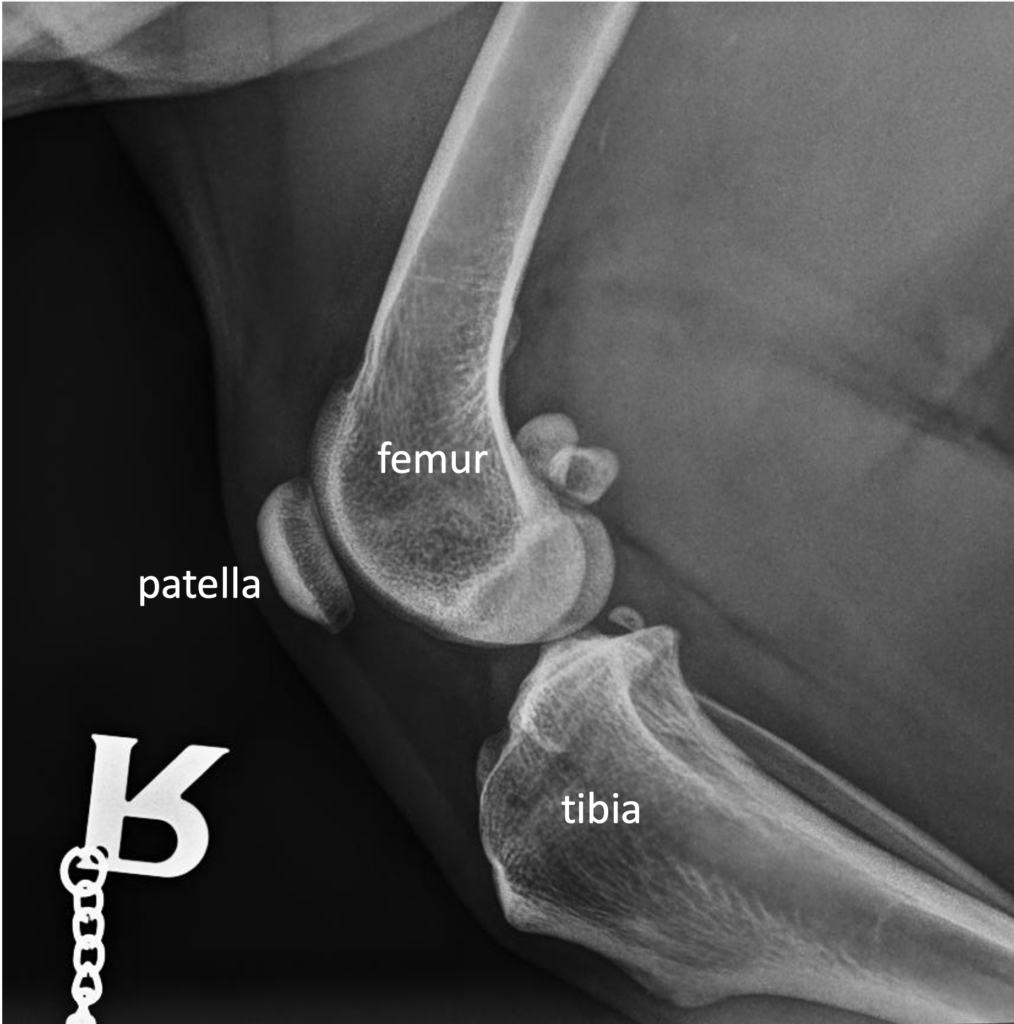

The stifle joint is the equivalent of the human knee joint. The main joint is between the femur and tibia, but there is also a joint between the femur and patella.